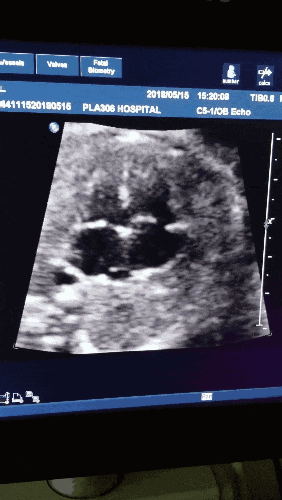

14週目に超音波検査を受け、他は正常でしたが、胎児の心拍数が90強と低く、医師から「この胎児の心拍数は遅すぎる」と言われました。

妊娠初期から中期にかけて、超音波検査のたびに、胎児の心臓の状態は必ず調べなければならない項目の一つであり、胎児の心臓の拍動の値も超音波検査の成績表に書かなければならない項目の一つであり、この時期の胎児の心臓の状態は2種類の結果として見られる。胎児の心臓が動いているということは胎児が生きているということであり、胎児の心臓が消えているということは子宮内で胎児が死亡しているということである。しかし、この間に胎児心拍に重大な異常が発見されたり、胎児低酸素症の重症例が発見されたりしても、自然の成り行きに任せ、胎児心拍停止後に陣痛を誘発する以外にできることはありません。

胎児の心拍が90回というのは確かに正常範囲外ですが、この先どうすればいいかというと、自然の成り行きに任せるとしか言いようがありません。胎児が正常に発育していれば観察を続け、胎児の状態が悪ければ中絶することになります。

聴診器で胎児の心臓の音を妊婦の腹部で聞くことができるのは妊娠17週までで、正常妊娠の場合、最初の胎児心拍モニタリングは基本的に妊娠30週以降に行われると言われています。しかし実際には、正常妊娠の場合、閉経後42日以降に子宮腔内の胎児の芽や胎児の心管の拍動が超音波検査で確認できる。受精卵が遅くても、閉経49日後から56日後までには超音波検査で子宮内に胎児心拍が確認できます。月経停止後56日を過ぎても子宮内の胎児心拍や胎芽が確認できない場合は、基本的に胎児不育症と診断されます。ほとんどの場合、妊娠6~7週には超音波検査で胎児の心拍が画面に確認できますが、聴診器で聞いてもほとんど聞こえないほど微弱です。特に家庭用の胎児心音モニターでは、聴診器で胎児の心臓をモニターするには妊娠16週近くかかります。妊娠14週では、超音波による胎児の心拍数は1分間に約90しかなく、これは実に遅すぎるため、胎児が低酸素症やその他の問題を抱えているかどうかを判断するために、医師によるさらなる検査が必要である。正常な胎児の心拍数は少なくとも毎分120回であるべきで、多少遅くても毎分110回を下回ってはならない。

14週目の胎児の心拍数は1分間に120~160回であるべきですが、これには個人差があります。その差が小さく、不快感がない限り、心配する必要はありません。

正常な状況下では、胎児の心拍数は毎分110-160回であり、現在の妊娠週数は小さく、胎児の心臓と神経系の発達はまだ完全ではなく、超音波検査で赤ちゃんの胎児の心拍数が遅いことがわかり、それはまた一過性である可能性があります。心臓超音波検査でもう一度見てみましょう。

正常な胎児心拍数は110-160の間であるべきで、あなたの胎児心拍数90は正常ではありません!